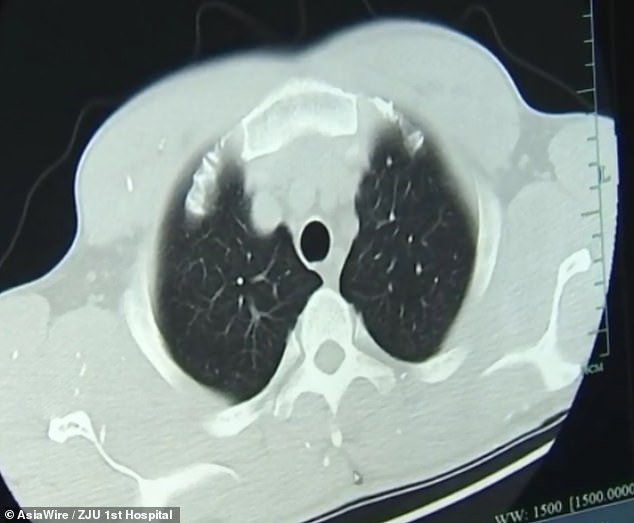

Dr Huang Jianrong, from the Affiliated Hospital of Zhejiang University School of Medicine, ordered brain and chest MRI scans.

These revealed that Mr Zhu’s brain and chest were riddled with cysts of the pork tapeworm.

Dr Huang said: ‘He not only had numerous space-occupying lesions in his brain, he also had cysts in his lungs and chest muscles.